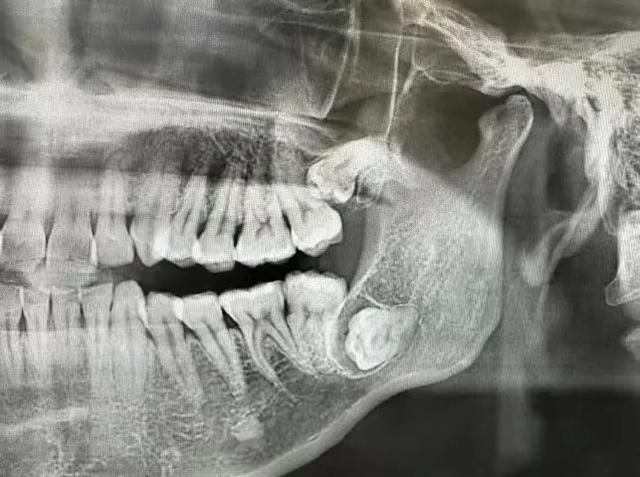

您下面智齒斜著長的,跟前面的第二磨牙經(jīng)常性食物嵌塞,把第二磨牙的鄰面蛀壞了,拍個片子看看吧。

您兩邊的智齒都把前面的第二磨牙頂壞了,治療計劃是拔除智齒,治療第二磨牙,要來好幾次了,費用也不低。

鄰牙損壞:

智齒生長可能對鄰牙造成擠壓,導致鄰牙損壞或移位。智齒與鄰牙之間容易嵌塞食物,難以清潔,長期下來可能導致鄰牙齲壞。

生長空間不足:智齒在生長過程中可能由于空間不足而引發(fā)疼痛、腫脹等癥狀,甚至可能侵犯鄰牙,導致牙齒錯位或擁擠。這種情況下,智齒需要拔除。

智齒阻生:阻生智齒是指智齒在萌出過程中受到阻礙,無法完全萌出至正常位置。這類智齒容易引發(fā)智齒冠周炎,且難以清潔,可能導致齲齒等問題,因此需要拔除。

影響其他牙齒:智齒的生長可能對鄰牙造成擠壓,導致鄰牙損壞或移位。在這種情況下,為了保護其他牙齒的健康,需要拔除智齒。